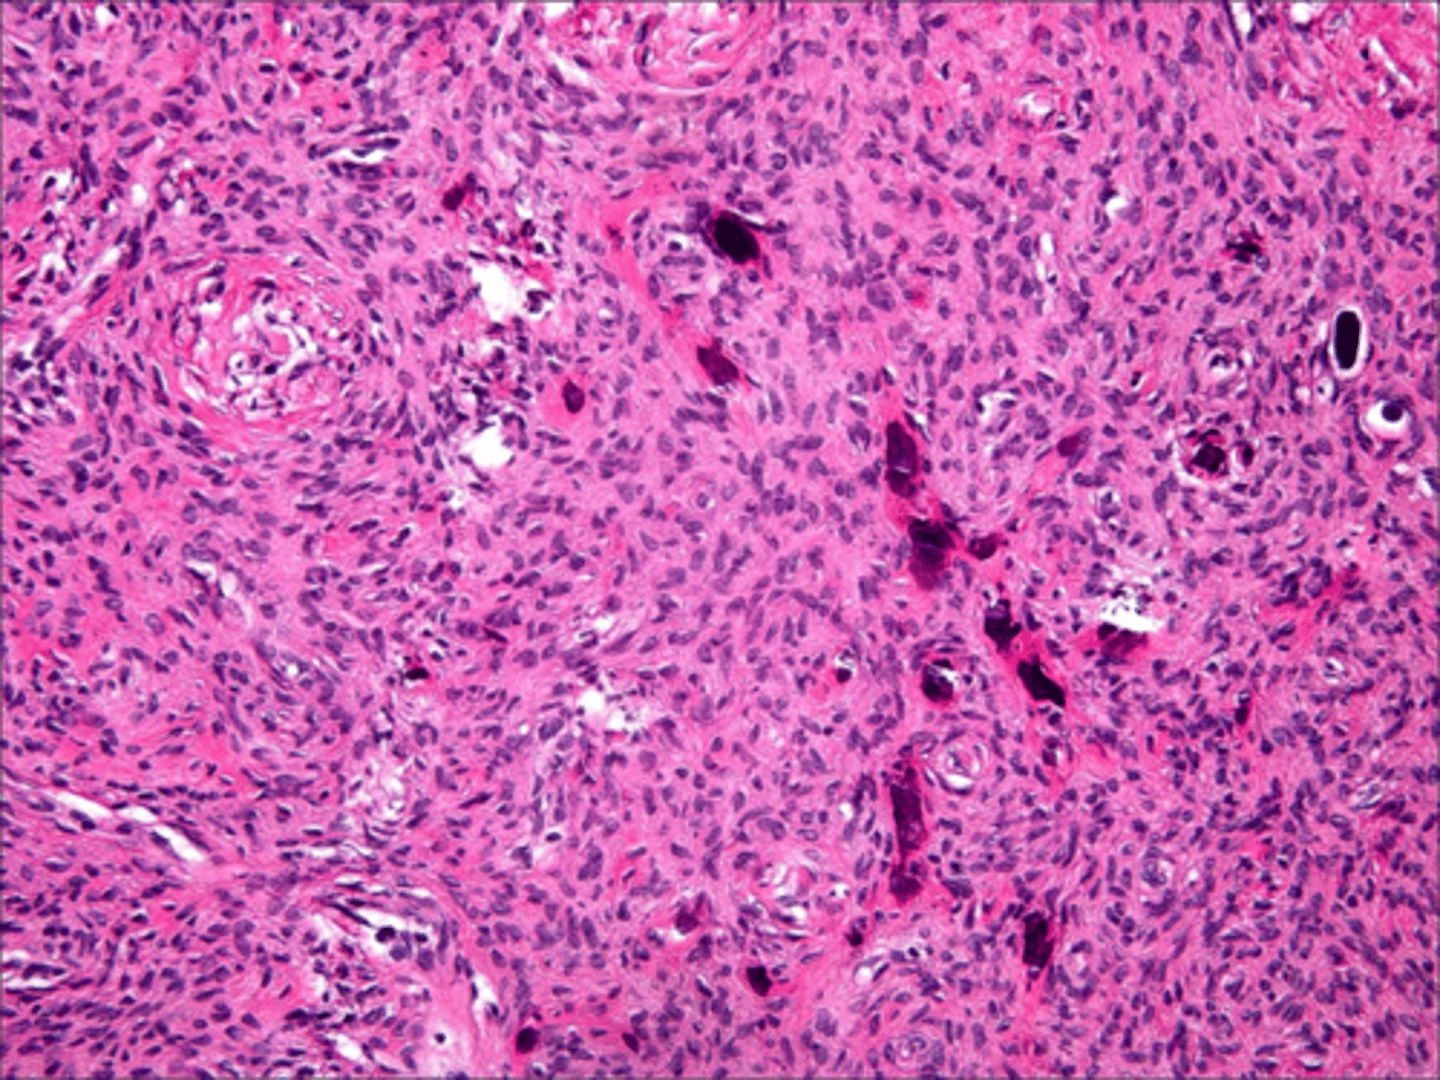

Neurofibroma

Patient presents with yellowish nodule on the dorsal tongue and gingiva. Histopathology shows interlacing bundles of spindle-cells with wavy nuclei. Patient also has several nodules all over the body that vary in size. What do you suspect the oral presentations to be?

Neurofibroma

interlacing bundles of spindle-cells with wavy nuclei is associated with what pathology?

local surgical excision

treatment for Neurofibroma: